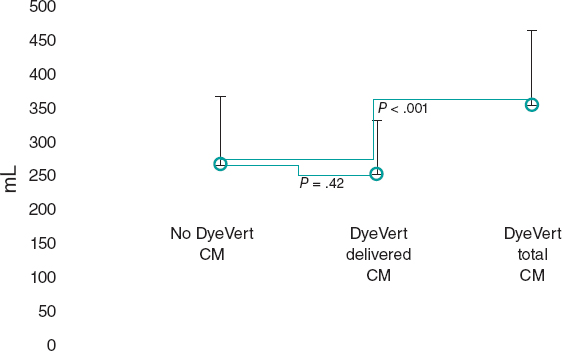

In order to protect the stent from the deformation by the tip of guiding catheter, the Guideliner guiding catheter extension device was used (Vascular Solutions, Inc., Minneapolis, Minnesota, United States). One semi-compliant balloon of 2.5 mm in diameter was advanced towards the proximal segment of the right coronary artery where it was inflated. It was then that the Guideliner device was advanced and the inflated balloon was slightly pulled (anchoring) by placing the tip of the guiding catheter extension device into the proximal segment inside the displaced stent (figure 2).

Figure 2. Advancement of the guiding catheter extension device towards the proximal segment of the right coronary artery.